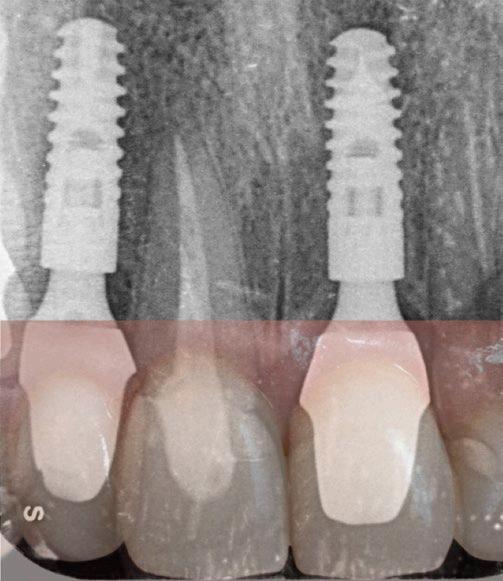

Jak už bylo dříve zmíněno, diagnostická fáze hraje zásadní roli, a proto musí být provedena s maximální

pečlivostí. Zahrnuje nejen posouzení stavu jednotlivých zubů, ale také analýzu rizikových faktorů spojených s celkovým zdravotním stavem a životním stylem pacienta. Pro ilustraci této problematiky ukazují obrázky 1.1 a 1.2 diagnosticko-terapeutický postup, který navrhuje možné léčebné řešení a aktivně zapojuje pacienta do rozhodovacího procesu. Tento přístup zajišťuje, že je pacient plně informován o dostupných terapeutických možnostech, což mu umožňuje činit kvalifikovaná rozhodnutí o svém orálním zdraví.